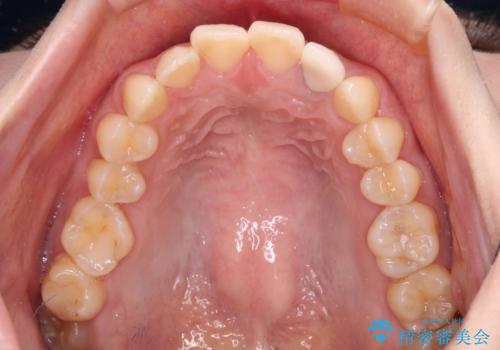

- 根管治療後に10年以上経過し、変色した前歯を気にして来院された患者様です。

根管治療はやり直さずに、ファイバーポストを使用した土台を植立してオールセラミッククラウンにて補綴することとしました。